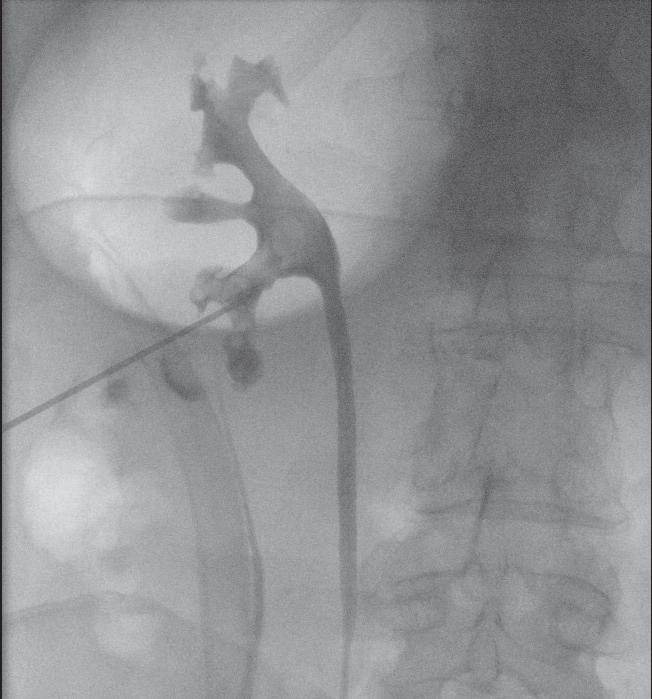

Miniperc 1: Kontrastmitteldarstellung der Kelche und des Nierenbeckens sowie Punktion.

Miniperc 2: Zugang mittels Einschrittdilatators.

Miniperc 3: Finales Bild mit antegrader DJ-Anlage.

Zeigt sich eine ausgeprägte Nephrolithiasis mit einer Größe von über 2 cm, so ist eine PCNL (perkutane Nephrolitholapaxie) empfehlenswert. Diese wird in der Regel mit rigiden Endoskopen durchgeführt und erlebte in den letzten Jahren eine sehr positive Entwicklung. Während in der Vergangenheit klassischerweise Endoskope mit einem Durchmesser von 20 Charrière (Ch.) und Zugangsschäfte von 24-32 Ch. zum Einsatz kamen, hat die zunehmende Verfügbarkeit von miniaturisierten Instrumenten dazu geführt, dass auch größere Steine in der Niere minimalinvasiv bei kürzeren stationären Aufenthalten als früher behandelt werden können. Die PCNL ist deshalb heute kein allgemeingültiger Standard mehr, sondern wird durch die Mini-PCNL, UltraminiPCNL oder Mikro-PCNL verdrängt. Mini-, Ultramini- und Mikro- beziehen sich dabei auf die durchschnittliche Größe der Instrumente. Je kleiner der Durchmesser der Geräte ist, desto geringer das Trauma und somit auch das Blu-

tungsrisiko. Ein kleinerer Durchmesser bedeutet aber auch längere OP-Zeiten. Grundsätzlich wird der Zugang durch die Haut mittels einer entsprechenden Nierenpunktion gelegt (siehe Abbildung, S. 23). Die exakte Positionierung der Punktionsstelle sollte mittels Punktionssonografie und idealerweise kombiniert mit einer Röntgendurchleuchtung erfolgen. Dadurch können die Lage des Konkrements und die Beschaffenheit der Niere besser beurteilt bzw. eingeschätzt werden.9 In der Folge werden die Steine unter Verwendung eines Lasers oder eines Lithoklasten (unter Druckluftwirkung können Steine zerkleinert werden) fragmentiert und die einzelnen Konkremente ausgespült. Dabei zeigten sich bereits früh in der Anwendung dieser Operationstechnik vielversprechende Ergebnisse, sodass die Komplikationsrate mittlerweile überschaubar und die Steinfreiheitsrate hoch ist.10